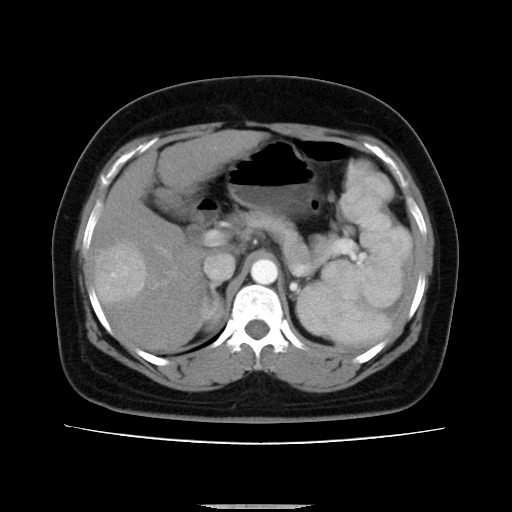

标题: CT14225:女性46岁。当地B超示肝内占位,来我院作CT检查。请 [打印本页]

标题: CT14225:女性46岁。当地B超示肝内占位,来我院作CT检查。请

肝内结节强化特点符合原发性肝癌表现,脾脏改变考虑为增大及先天发育所致。

动脉期病原灶明显强化高于肝密度且中央有无强化区,静脉期强化程度下降明显,延迟低于肝密度,考虑肝腺瘤可能性大,

肝内结节强化特点:快进快出符合原发性肝癌表现

非常典型,肝ca,脾脏先天性发育异常,脾大

此患者虽然符合快进的特点,却不符合快出的特点,因为门脉期几乎是等密度,不符合肝癌的增强表现,所以我考虑肝局灶性结节增生可能性大

肝内结节强化特点符合原发性肝癌表现。脾大。

快进快出,符合肝癌表现。脾脏改变考虑为增大及先天发育所致。